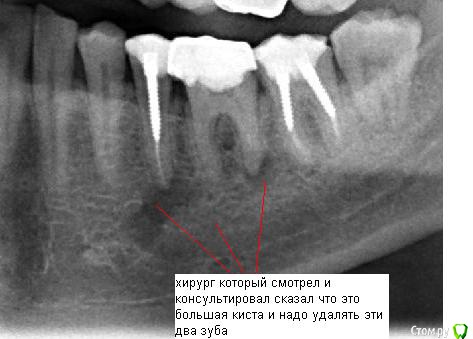

SergeySergey Опубликовано 16 октября, 2015 Поделиться Опубликовано 16 октября, 2015 Киста - что делать ? Заныла десна под 5 и 6 зубом, сделал рентген, результат - киста под 2-мя зубами 5 и 6 и еще киста между корнями у 6-ки.5 зуб болезненно реагирует на постукивания. Хирург и мой постоянный лечащий врач-терапевт говорят - нужно удалять два зуба и кисту, лечить не получится и обосновывают следующим:Проблема что 5 зуб со штифтом и вытащит штифт не возможно, а 6 проблемный в плане перелечивания, так как в канале есть инородное тело (возможно фрагмент инструмента), достать нереально а очаг как раз на верхушке этого корня, передние каналы 6 зуба тоже плохие (не видны), скорее всего не проходимы. Вероятно лечился резорцин-формалиновым методом и очень давно (1995-97 гг) Еще в другом месте врач-терапевт консультировал и говорит - не удалять а лечить все вопросы решаемые - штифт из 5-ки можно извлечь, если не извлечется штифт, то хирург доберется к кисте через челюсть, а 6-ку каналы можно вскрыть. и все вылечить за несколько месяцев и несколько посещений. Ваше мнение ? Что делать идти не к своему врачу а к тому который возьмется или удалять как говорить мой врач и хирург ? Ссылка на комментарий